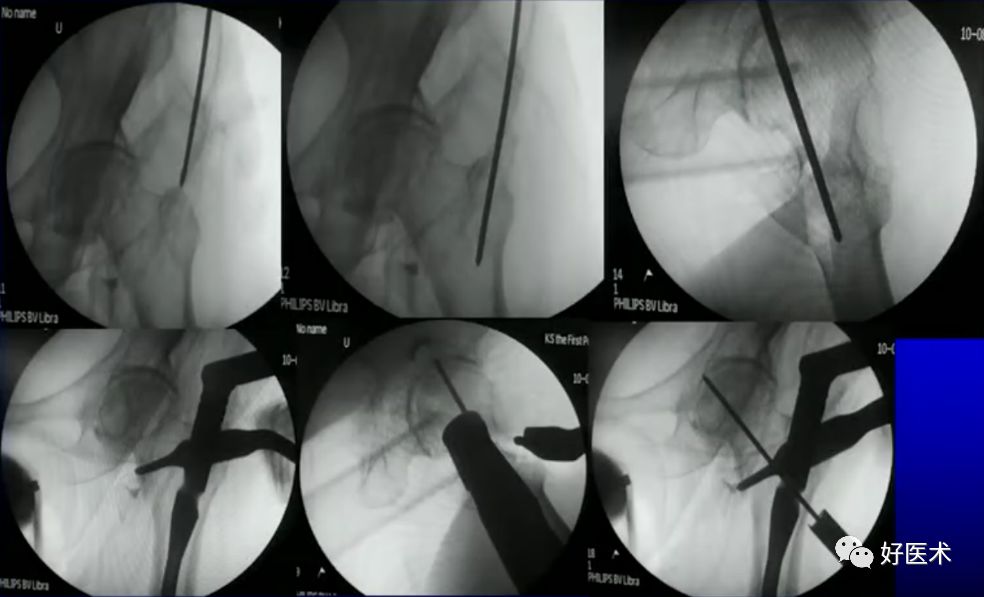

病例二:女 75岁

术前复位:

定位:

术后:

病例三:女 82岁

四部分骨折,髓内钉,钢板

5.避免进钉点失误

进钉点偏外易造成髋内翻

头钉的尾部要置于外侧骨皮质外而不能埋入皮质下